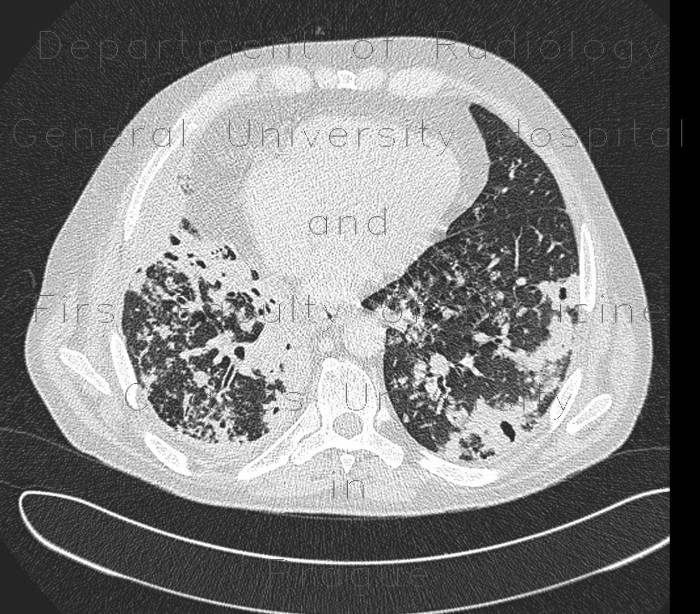

Lung tuberculosis, caseous pneumonia, HRCT

Multiple patchy infiltrates, some confluencing and cavitating, tree-in-bud, cavern.

Radiology image - Lung tuberculosis, caseous pneumonia, HRCT: Thorax, Lung: CT - Computed tomography